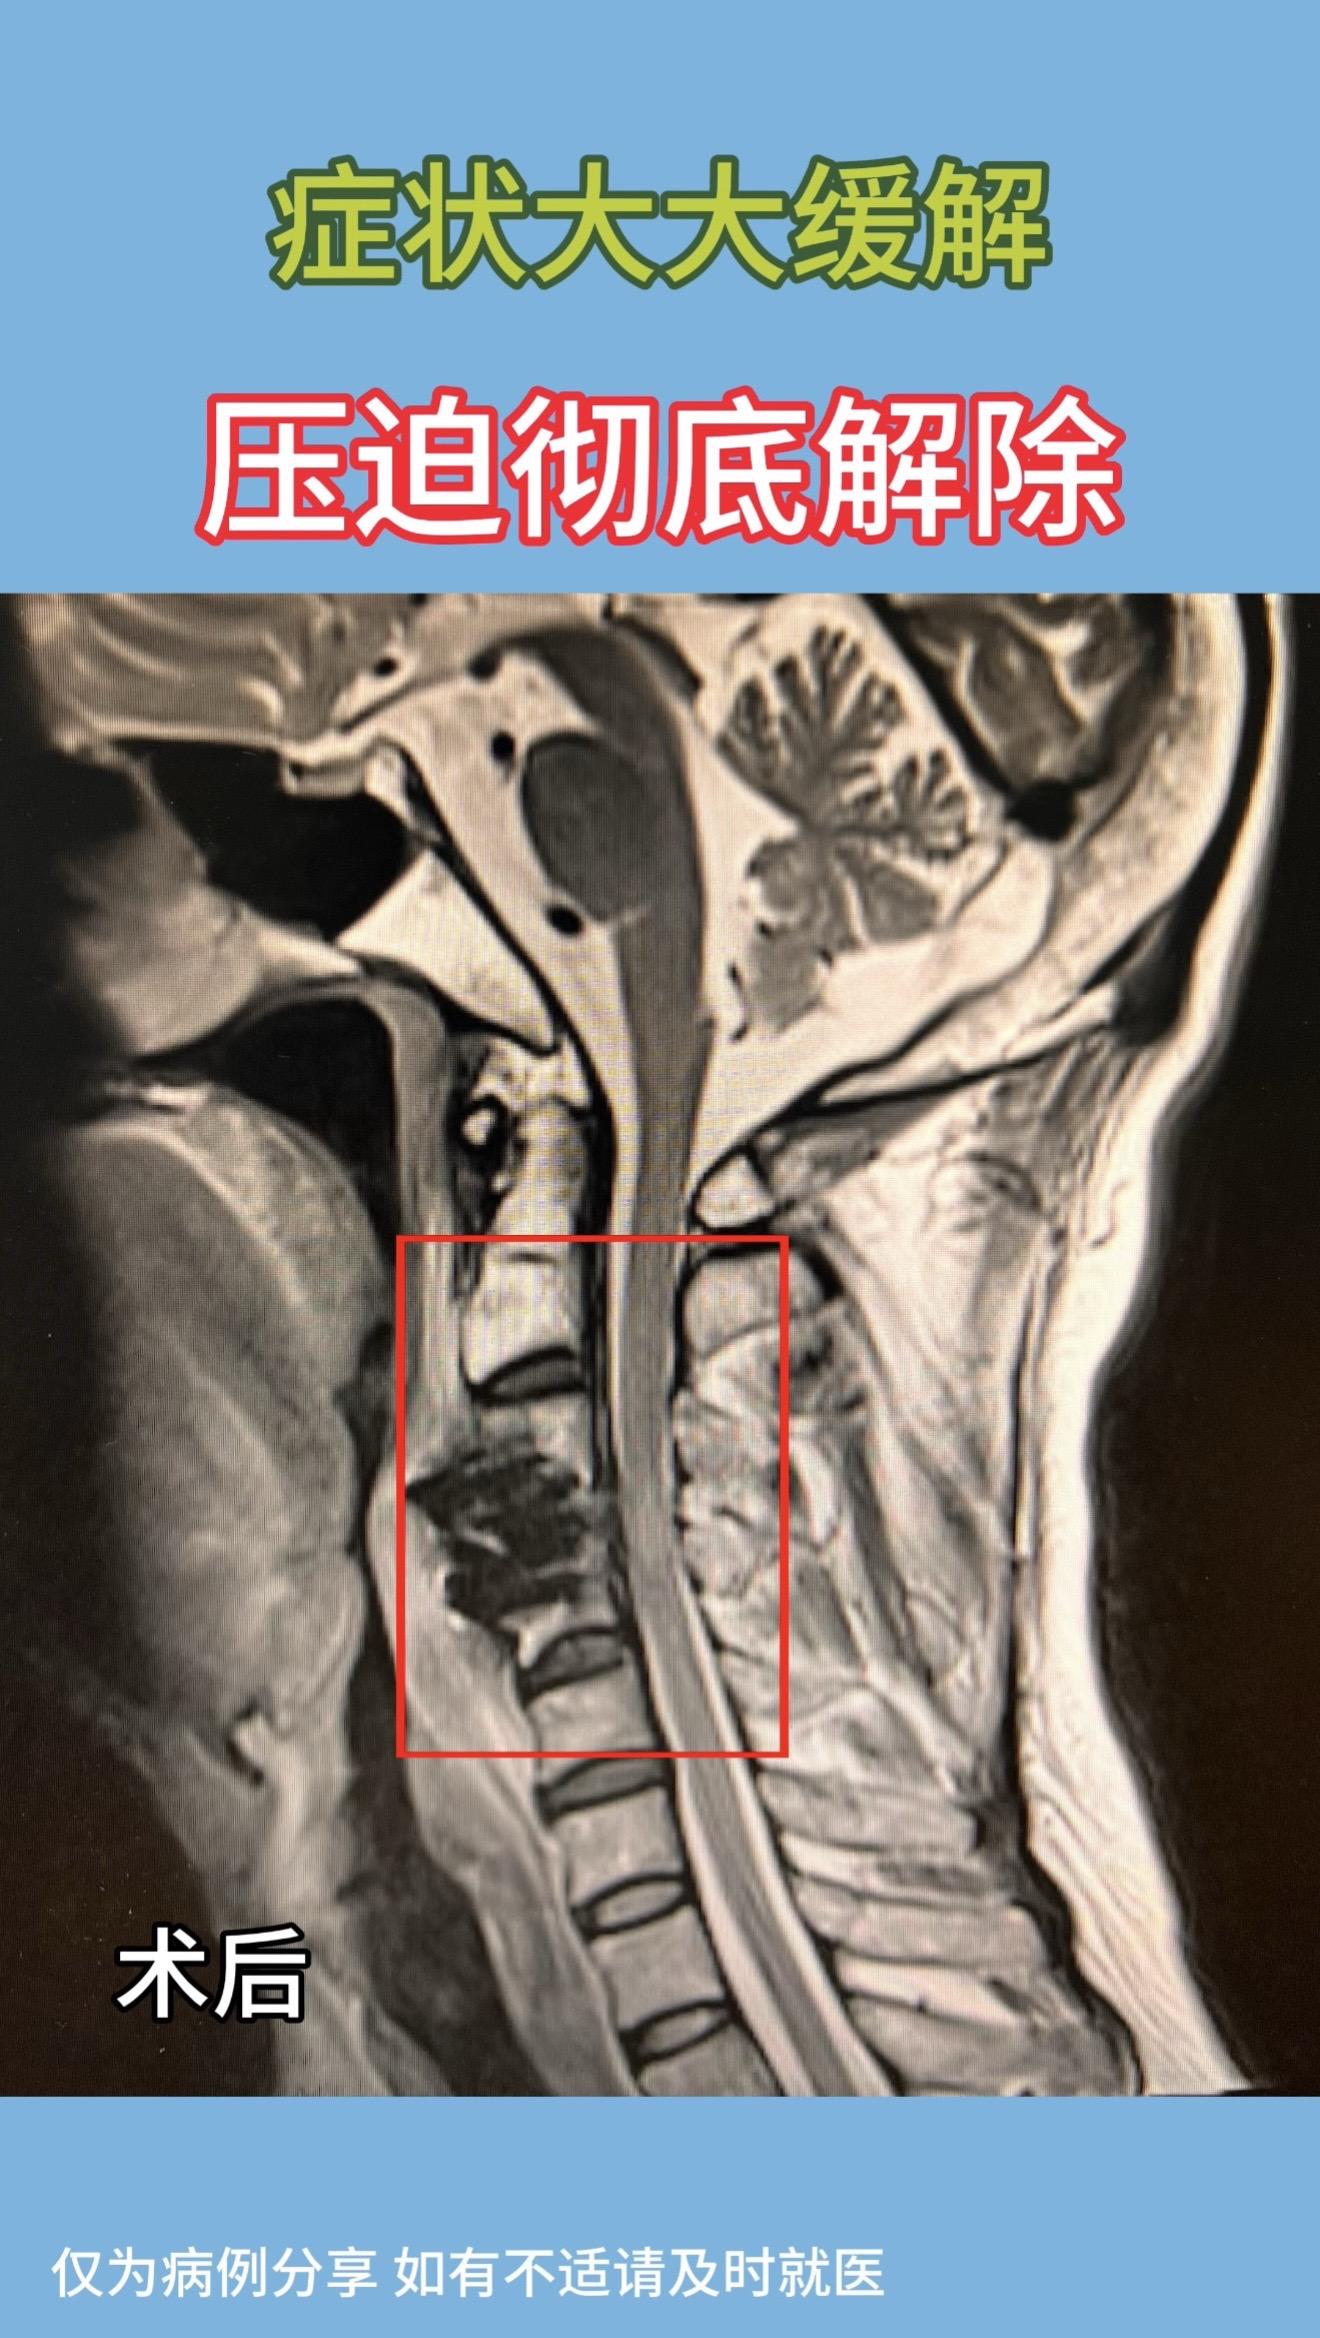

40多岁男性,右手无力、肌肉萎缩半年,右手持筷不能,只能用勺子吃饭。左手无力,症状较右侧稍轻。磁共振示高位颈3/4突出,脊髓信号改变。术后症状大大缓解,术后磁共振示压迫解除彻底。